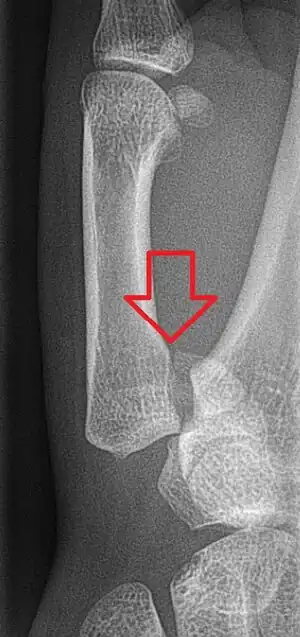

Bennett fracture

A Bennett fracture is a type of broken finger involving the base of the thumb, which extends into the knuckle joint.[4][1] Symptoms generally include thumb swelling and pain.[1] Associated injuries may include ulnar collateral ligament injury of the thumb or trapezium fracture.[1]

The cause is generally a force along the long axis of the thumb.[1] Diagnosis is supported by X-rays.[1] There is nearly always some degree of disruption of the carpometacarpal joint.[2]

Though these fractures commonly appear quite subtle or even inconsequential on radiographs, they can result in severe long-term dysfunction of the hand if left untreated. In his original description in 1882, Bennett stressed the need for early diagnosis and treatment in order to prevent loss of function of the thumb CMC joint, which is critical to the overall function of the hand.[7]